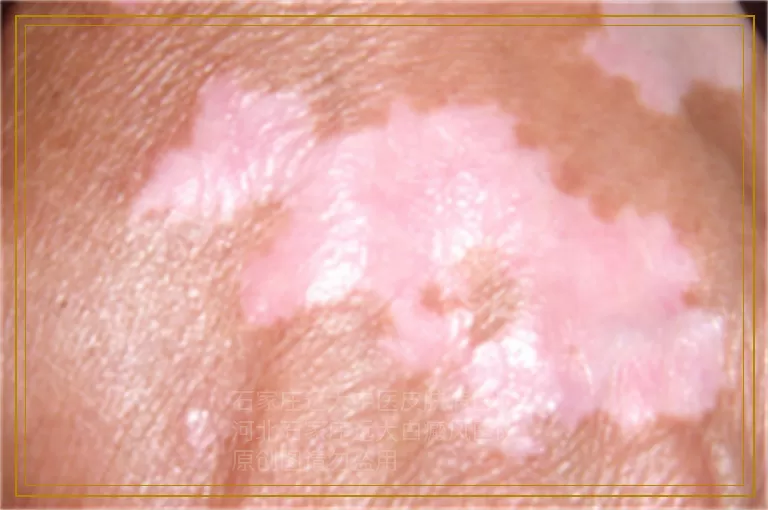

白癜风照完激光红红的是什么原因

不少白癜风患者在接受激光治疗后发现皮肤泛红,心里难免犯嘀咕:这到底是好现象还是出了什么问题?其实照完激光后发红是比较普遍的情况,理解背后的缘由能帮助大家更安心地配合后续疗程。激光治疗白癜风主要依靠特定波长的光束精准作用于白斑区域,这种能量穿透表皮层后会激发一系列生理反应,泛红正是组织响应治疗的直观表现之一。

从原理上讲,308准分子激光或窄谱UVB等光疗手段,核心机制在于激活休眠的黑色素细胞并促进其增殖迁移。当光束照射到皮肤时,局部温度轻微上升,毛细血管随之扩张以增加血氧供应,这种血流变化就呈现为我们肉眼可见的红润色泽。打个比方,就像运动后脸颊泛红一样,是机体代谢加快的外在信号。对于白癜风患处而言,这种反应恰恰说明光能量已被有效吸收,正在唤醒那些功能减弱的色素细胞。

需要区分的是正常治疗性发红与异常反应。理想状态下的红斑应在照射后数小时内出现,颜色均匀如浅玫瑰色,触摸无显著灼热感,且24至48小时内逐渐淡化。这种反应伴随轻微干燥或细屑属于修复过程中的伴随现象。若出现深红色斑块、边界清晰的肿胀,或患者自觉持续灼痛、瘙痒难忍,则提示光剂量可能超出当前皮肤的耐受阈值,此时需及时反馈给主治医师重新评估参数设置。